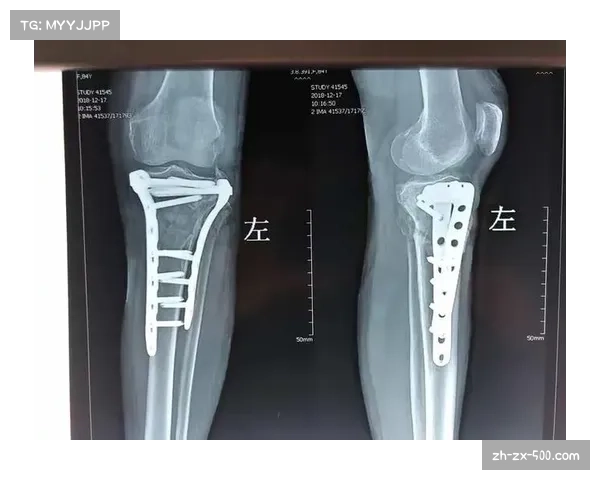

在实际手术操作过程中,主刀医师依次对骨折段进行复位、清理碎骨、稳定重建、固定植入。操作过程中要小心处理骨片、血管与神经组织,保持脊髓完整性,并避免造成术中出血或血肿压迫。术后还需立即进行成像检查确认内固定位置精准、骨折处复位良好。

在术后数周至数月期间,阿萨莫阿恢复情况被评估为“良好”:疼痛减轻、颈部活动度逐渐恢复、神经症状无明显加重、影像学显示骨折端持续愈合趋势。常规检查(如CT、MRI、X线)显示骨痂形成,内部固定装置状态稳定未见移位。